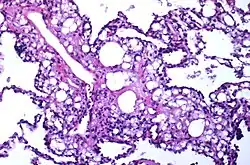

Numerous interstitial fat globules of varying size accompanied by inflammation and fibrosis is characteristic of chronic lipid pneumonia secondary to lipid aspiration. | |

Once inhaled, these fuels induce an inflammatory reaction in lung tissue. They are not metabolized by tissue enzymes, but undergo emulsification and become engulfed by macrophages which, with time, may disintegrate and release oily substances surrounded by fibrous tissue and giant cells.[8]